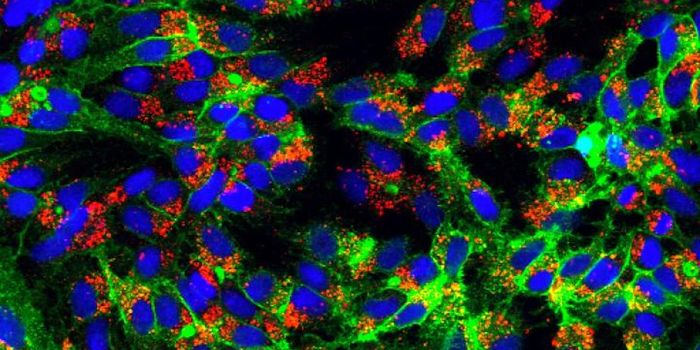

APR 04, 2022Cell & Molecular BiologyAbout 1.5 million new HIV infections are thought to have occurred last year, and while COVID-19 has dominated concerns a ...